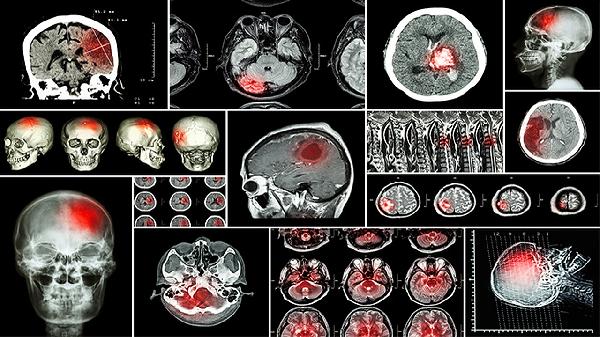

腦氙患者有恢復(fù)的可能性嗎?

腦疝患者有恢復(fù)的可能性,但具體恢復(fù)程度與腦疝類型、病情嚴(yán)重程度及救治及時(shí)性密切相關(guān)。腦疝通常由顱內(nèi)壓增高導(dǎo)致腦組織移位引起,可分為小腦幕切跡疝、枕骨大孔疝等類型。